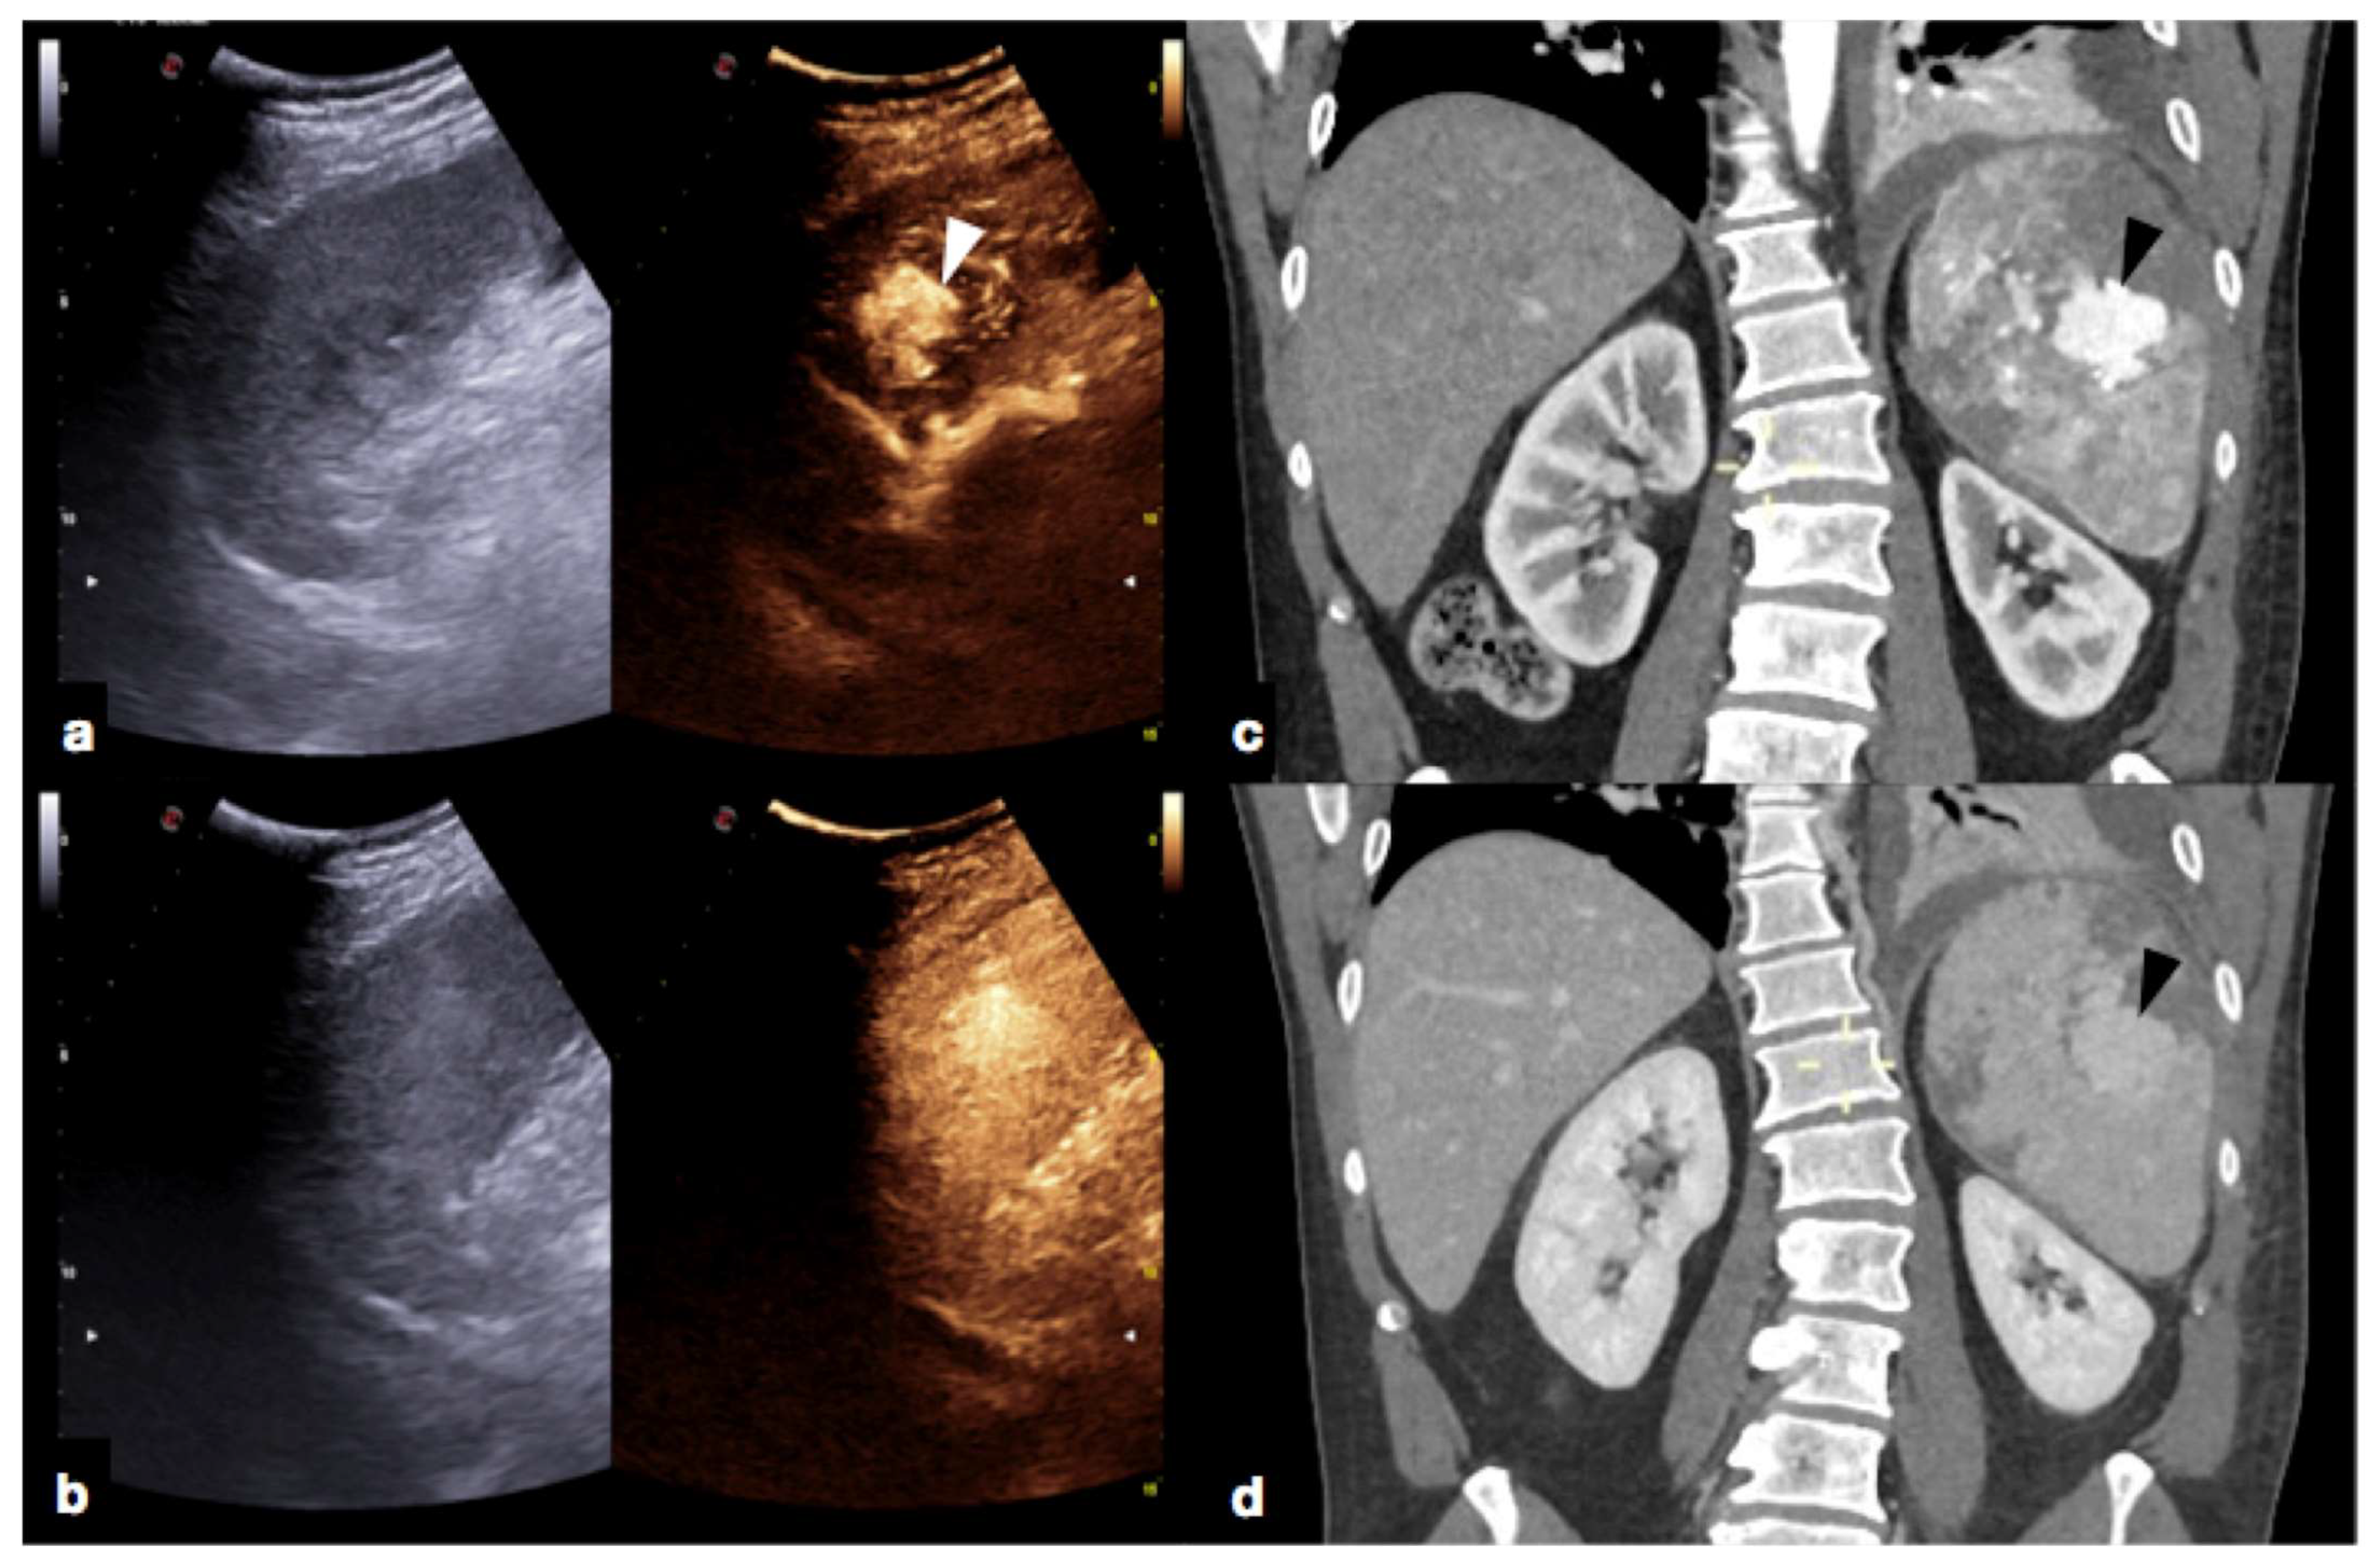

Figure 19.

High grade traumatic splenic injury with vascular complication. Arterial (a) and venous (b) phase CEUS examination in a 25−year-old patient admitted at the emergency department for blunt abdominal trauma, showing multiple splenic lacerations and a voluminous arteriovenous fistula (white arrowhead). Subsequent arterial (c) and portal vein (d) phase contrast-enhanced CT scan further confirmed the diagnosis (black arrowhead).